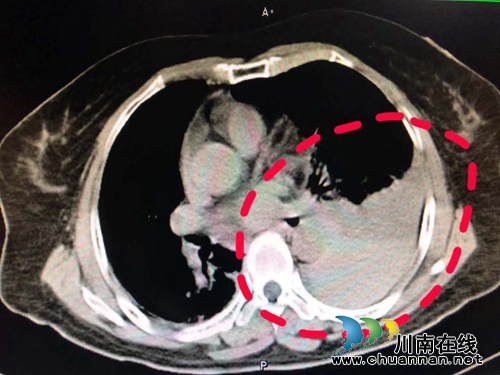

“患者来的时候,大概是晩上8点,我们赶紧安排她进行急诊CT检查,检查发现患者颈部、纵隔、胸腔出血,出血量约500ml,需要手术止血。”心胸外科副主任刘浩副教授说。

完善了相关检查后,刘浩带领医护人员连夜为胡老太太进行了急诊手术。“术中我们发现患者颈内静脉破裂,由于出血迅速并且量大,形成的血凝块暂时封闭破口让出血减慢,给了我们修䃼缝合血管的机会。术中我们还发现血管破口旁边有一伤口通向胸腔,导致纵隔胸腔大量积血。”刘浩告诉小编。